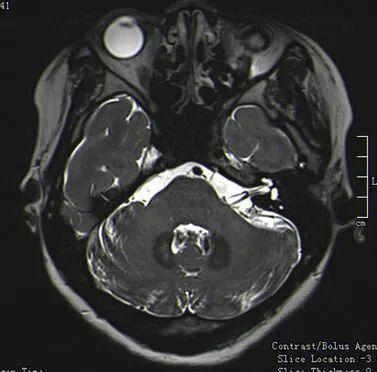

第二例 面肌痉挛何某,女,36岁,“左面部不自主抽动2年,加重3个月”入院

左侧面神经与小脑前下动脉与小脑后下动脉关系紧密

注意了,这是两根不同的血管

血管穿过面听神经之间

术中暴露小脑前下动脉和小脑后下动脉

剥开听神经可见细长面神经,小脑前下从面听神经之间穿出,并与小脑后下动脉被蛛网膜包裹形成系带

细长面神经可见系带形成的压迹

TEFLON棉垫开两根责任血管术后患者再无挤眉弄眼的表现